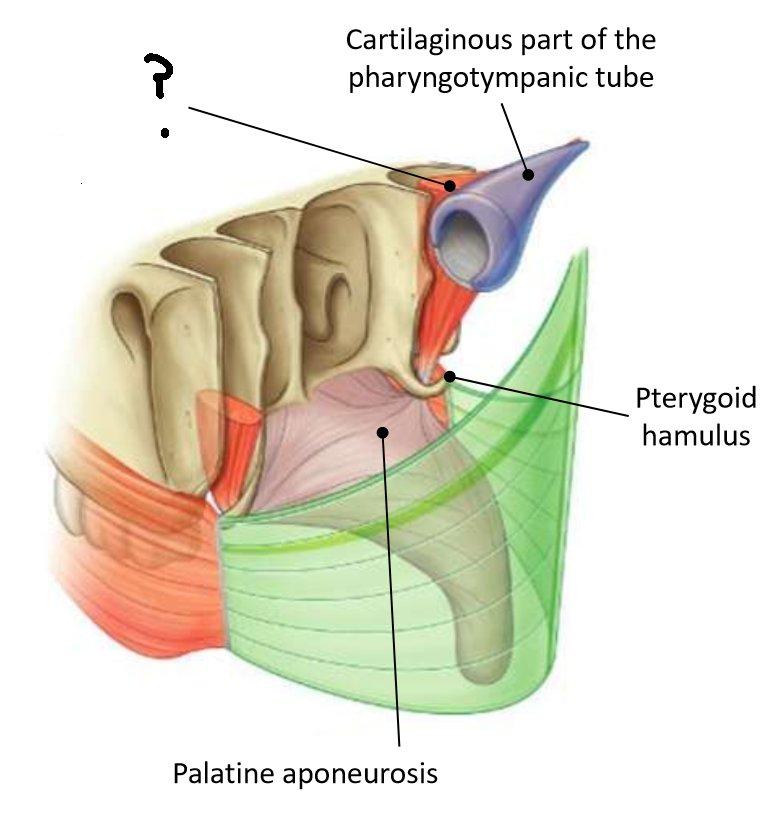

What does the pharyngotympanic tube connect?

middle ear and nasopharynx

What does the pharyngotympanic tube do?

equalises pressure on each side of the tympanic membrane

What are the two parts of the pharyngotympanic tube?

bony third near the middle ear, rest is cartilaginous

What muscle is this?

palatopharyngeus

What are the attachments of this muscle?

upper surface of palatine aponeurosis → deep pharyngeal wall

Which muscle is this?

tensor veli palatini

What are the two parts of this muscle?

muscular and fibrous

What is the function of this muscle?

tenses soft palate, opens pharyngotympanic tube

What innervates this muscle?

medial pterygoid nerve of mandibular branch of trigeminal

Which muscle is this?

levator veli palatini

What are the attachments of this muscle?

petrous part of temporal bone and pharyngotympanic tube → palatine aponeurosis

What is the function of this muscle?

lifts soft palate to close nasopharyngeal isthmus

What innervates this muscle?

pharyngeal branch of pharyngeal plexus of vagus nerve